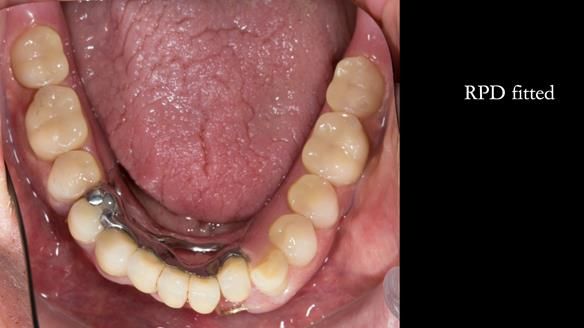

Instead, we made a Scandinavian-style, metal-based lower RPD.

It was made promptly, then relined gradually over the following year

to optimise fit, comfort, and support.

It’s worth saying that the lower denture in this case was made in the early days of Rowan and me using the Scandinavian approach. Rowan cast the metalwork himself for this denture.

Looking back, we would make this denture more hygienic now. The design and finish would be more refined and delicate, particularly when compared with the upper metalwork, which was made later using Chris Hesketh’s chrome work. I will discuss this in detail at the study club.

That said, the lower denture worked beautifully. It did exactly what it was meant to do, even though, by today’s standards, it looks a little agricultural.

This case was always about function, not aesthetics.

What matters is that the dentures worked.

The way Rowan lengthened the teeth — particularly in the upper RPD — to match the existing gingival recession on the remaining teeth was superb. The dentures sit naturally within the context of the rest of the mouth.

Most importantly, Ken could eat comfortably, speak normally, and get on with his life without thinking about his teeth. There were no ongoing problems. No drama. No repeated interventions.